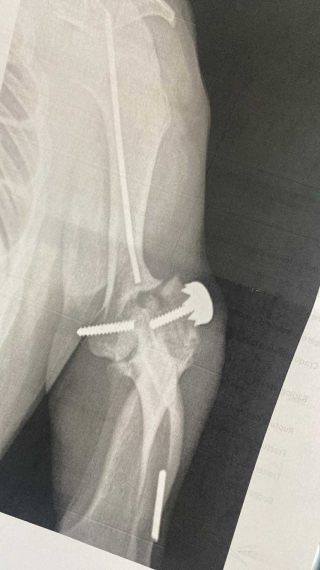

voxane61 a écrit : Mon chien c'est re fracturer le coude dont il c'est fait opéré il y a 2 ans . Tout à cassé la vis , la broche , l'os . Nouvelle opération mercredi. C'est la première fois que le vétérinaire voyait ça

Il commence à aller mieux , l'opération a été longue (4h ) et le réveil un peu dur ( il a 9 ans et demi ) .

Il n'ose pas encore posé sa patte mais il a retrouver l'appétit c'est bon signe .